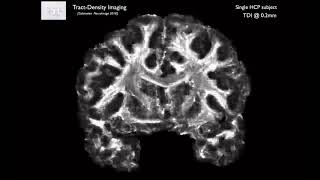

Diffusion (DTI): Diffusion: Diffusion Tensor Imaging and TBSS

36. Diffusion 1: Tour of DTI in FSL

37. Diffusion 1: DTI Basic Principles